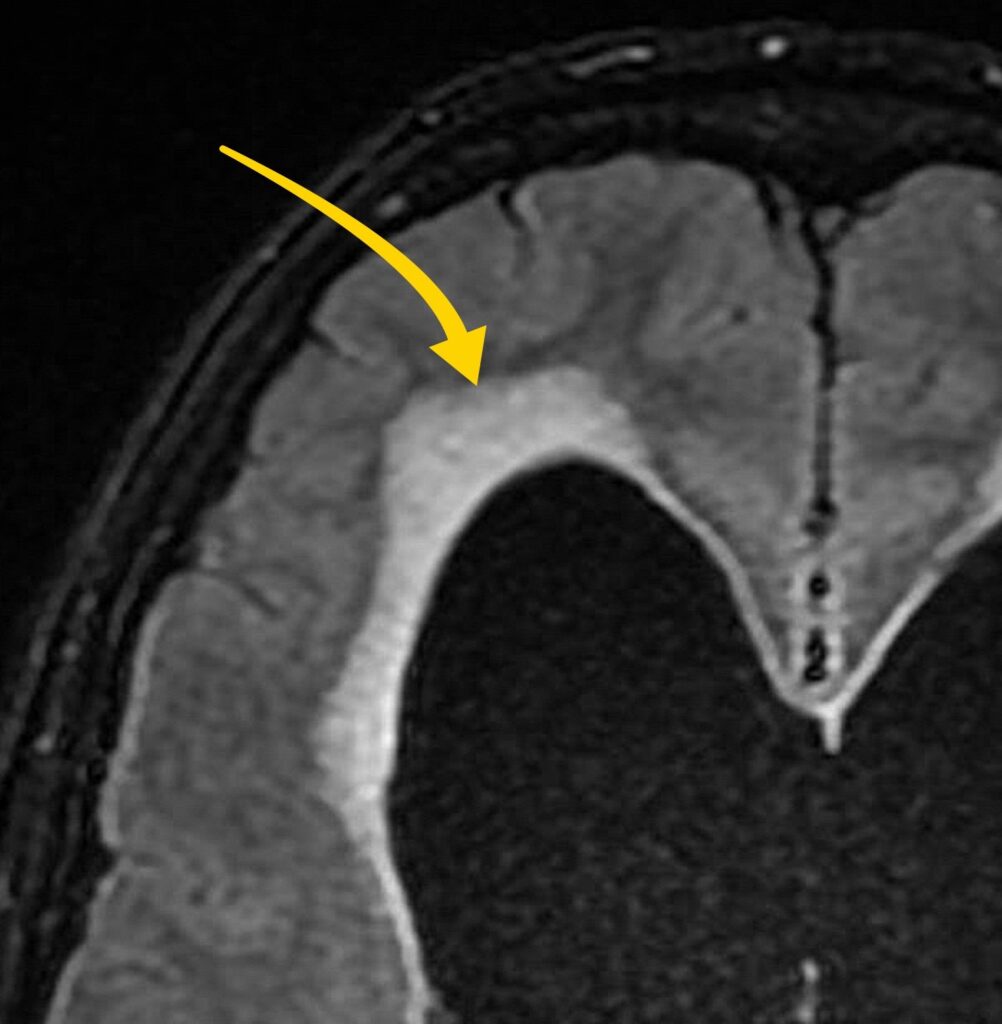

Going back to the FLAIR sequence, we see high signal surrounding the lateral ventricles—this is transependymal oedema, an important indicator of acute obstructive hydrocephalus.

What’s happening here?

- The blockage at the foramen of Monro disrupts CSF flow.

- Pressure builds up in the lateral ventricles.

- Fluid leaks into the surrounding brain tissue, causing oedema in the periventricular white matter.

This is a serious finding: it suggests acute hydrocephalus, which, if untreated, can lead to brain herniation and death.

Fluid leak in the context of acute hydrocephalus can lead to transependymal oedema and the appearance of hyperintensity on FLAIR images.